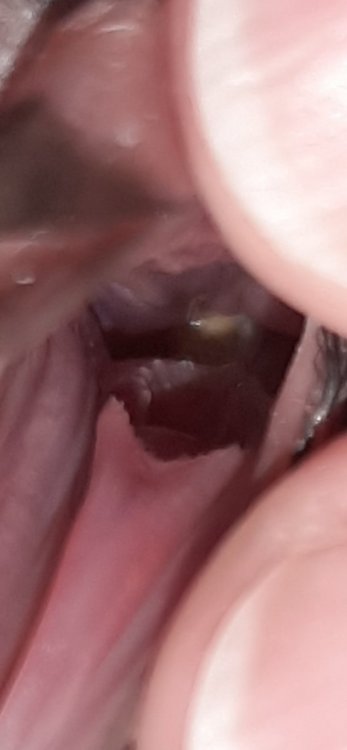

@маленький принц вот фото наростов сегодня и вчера. так и остаются, подаю метронидазол 1,5 мл 2 р/д и четверть нистатина уже неделю и один день. до этого орнидазол был 3 недели. метрогилом дента 2 р/д смазываю. хочу спросить нормально ли то что так долго лечу и не проходит?

@маленький принц увеличила Метронидазол до 1,8 мл, уже 2 дня на такой дозе. Метрогилом смазываю. Фото нароста прилагаю. Маленький, а все не уходит (он чуть больше, чем на фото)